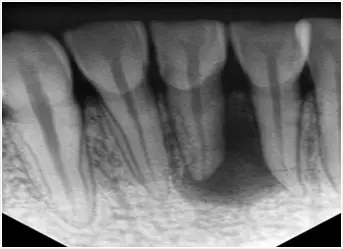

1、術(shù)前拍攝X線片

在根管治療過程中,在根管治療術(shù)前拍X線片,以幫助診斷,了解髓室的位置和根管數(shù)目及形態(tài),測量根管工作長度及日后隨訪和評價療效提供對比的依據(jù)。